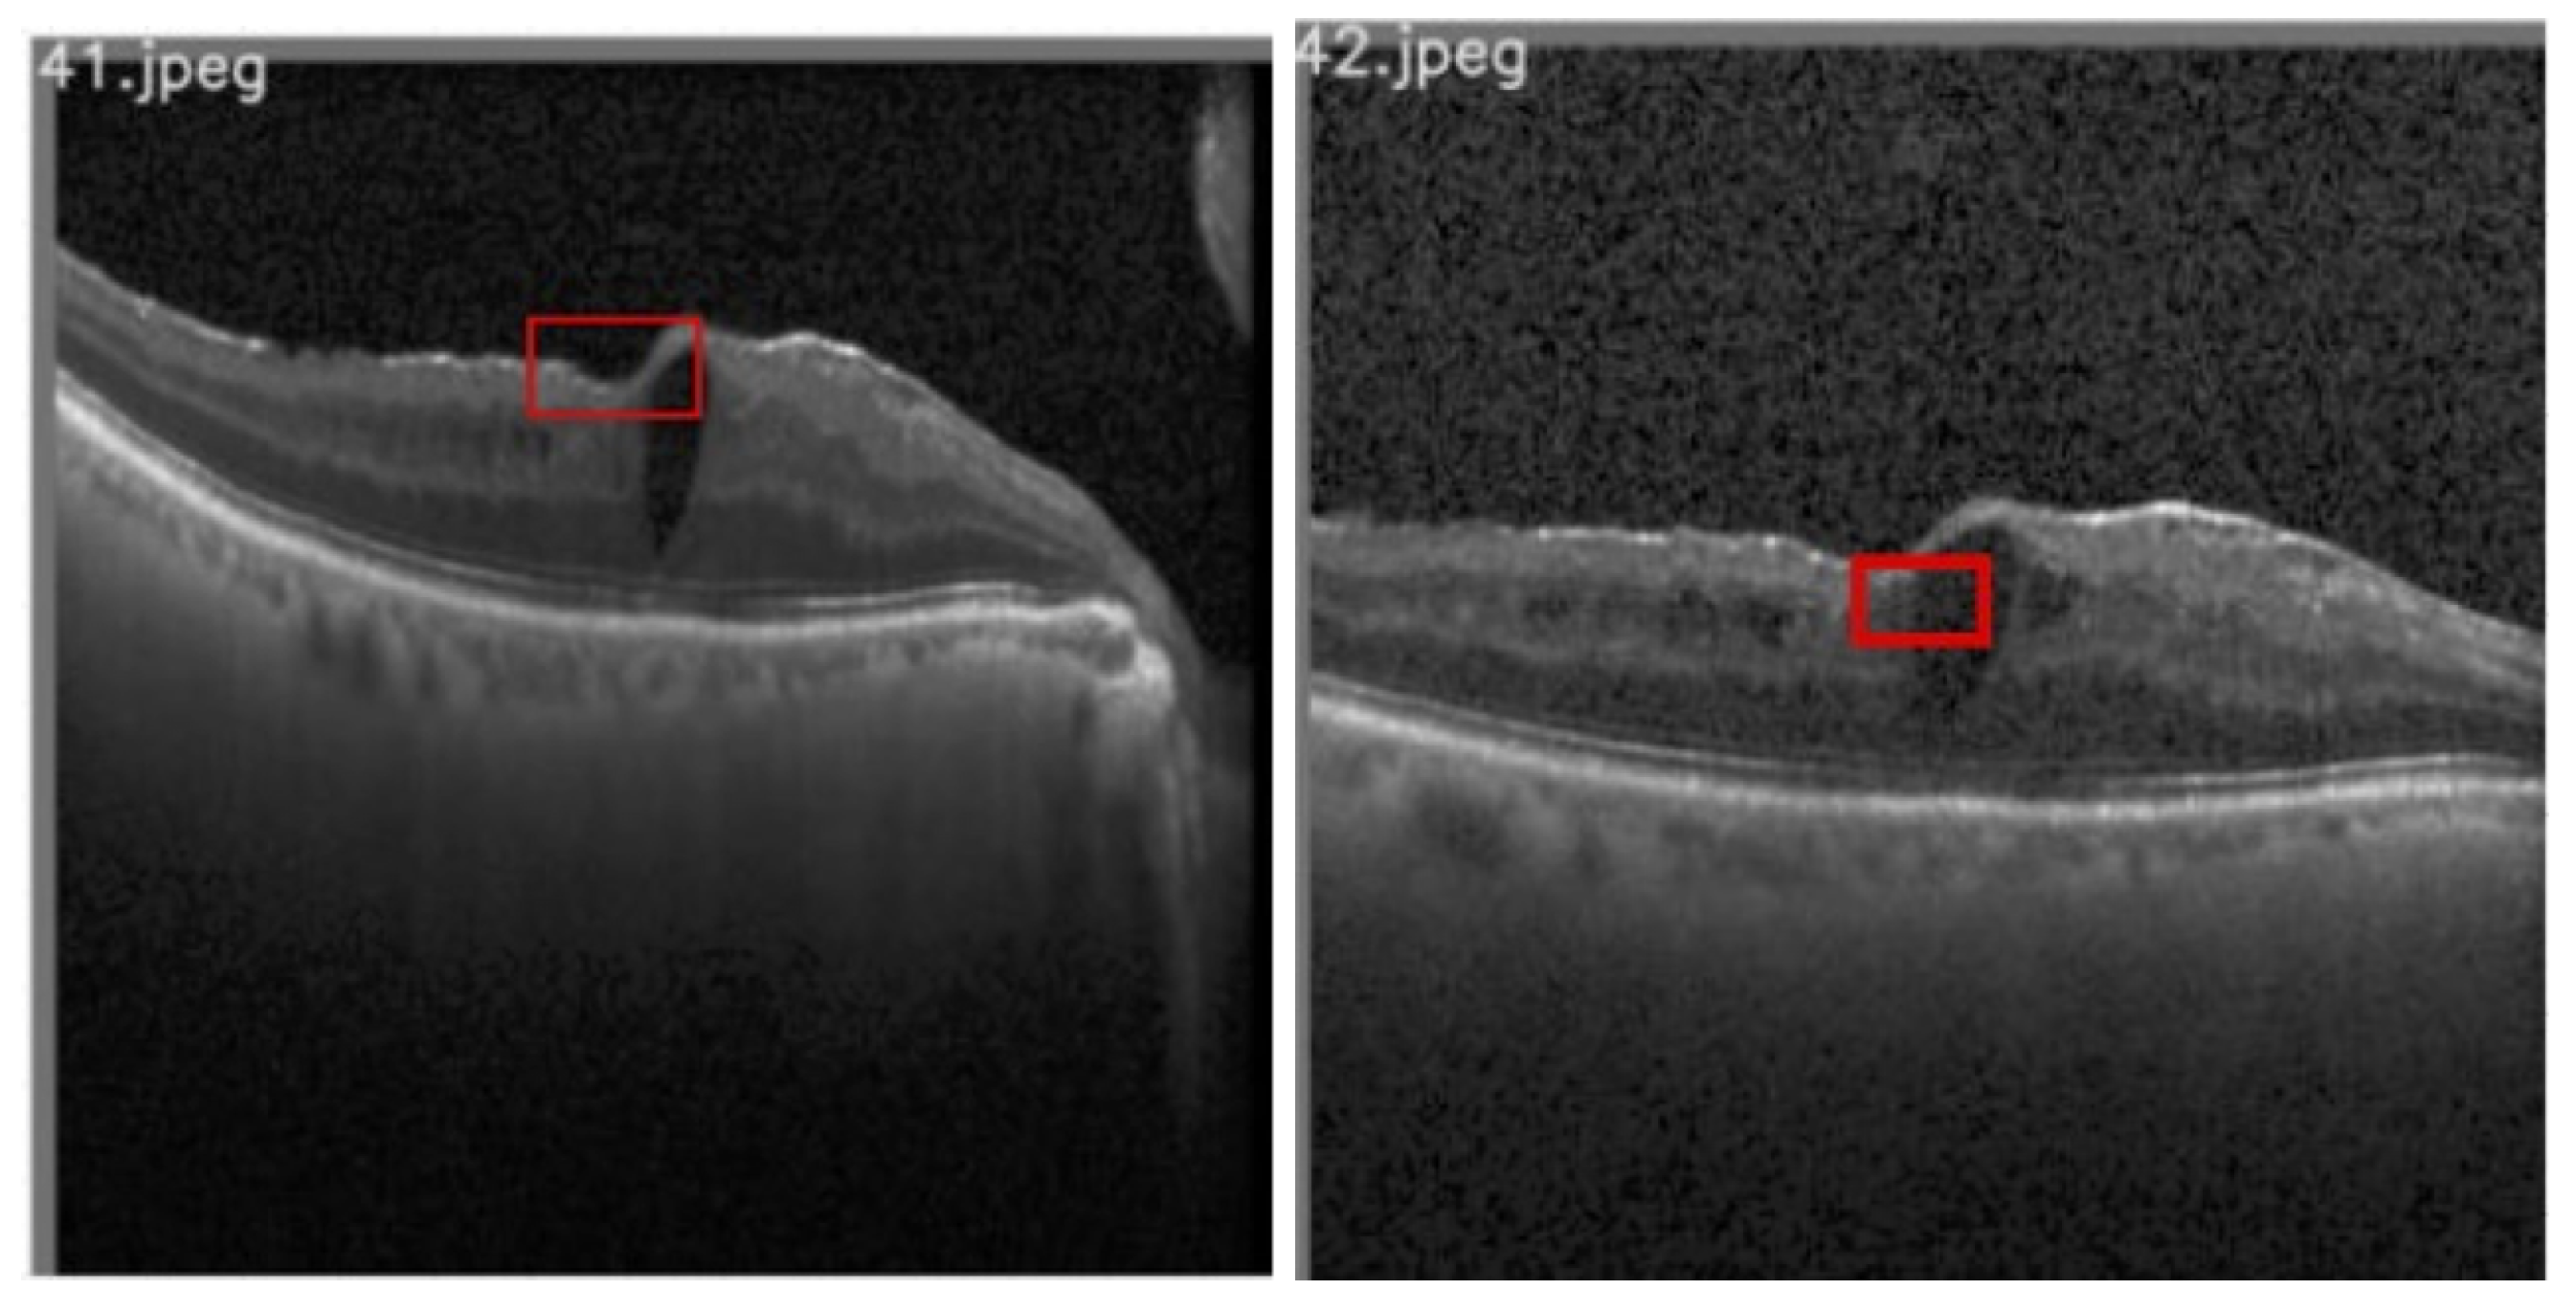

3.1.1. Disorganization of Retinal Inner Layers (DRIL)

3.1.2. Hyperreflective Focii (HRF)

3.1.3. Cystoid Space

4.3.1. DRIL

4.3.2. HRF

4.3.3. Cystoids